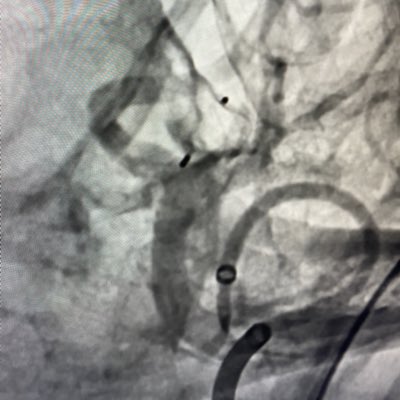

Anvil-shaped 11mm AComm aneurysm, t/w WEB 10x5. No residual filling, see ya! Eric R Smith @MV_Terumo Steve buzzell

15x13x12 mm unruptured basilar aneurysm, treated with a βWeb hat,β aka Web-coil embolization. Eric R Smith